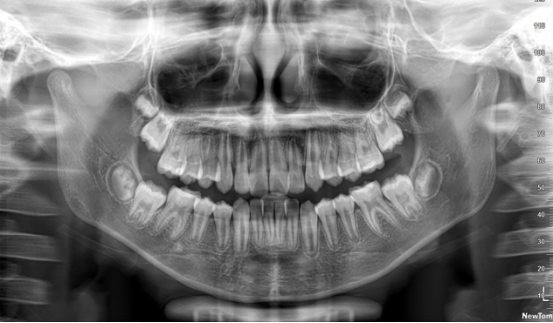

意大利NewTom是应用最新三维锥形束技术,采用平板探测器,利用锥形X线束只需要一次360度旋转扫描就能精确地获得全部图像信息,进一步增加图像的应用范围。

在不同的临床应用中可提供多种视野选择,从最小的5×5cm到最大11×13cm,医生能够在扫描前直接通过软件对目标区域选择视野。

该系统获取清晰图像同时辐射量最低。采用对患者和操作者最安全的Safe Beam技术,该技术能根据患者的年龄、体格自动调整辐射剂量并取得最佳的图像对比度。